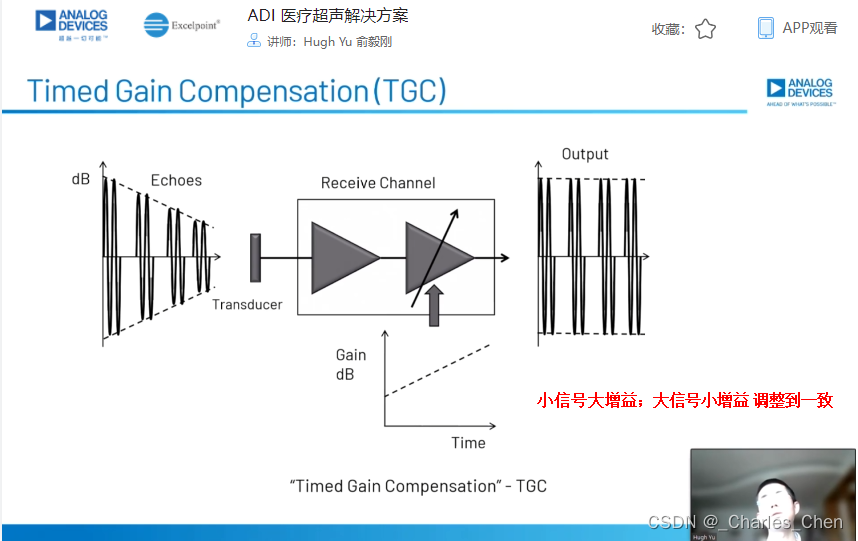

可变增益放大器(VGA)

VGA有时也称为时间增益控制(TGC)放大器,能够在整个接收周期内为接收机提供足够的动态范围。超声信号在体内大约每秒传输1540米,往返衰减率为1.4dB/cm-MHz。发射一个超声脉冲后,可立即在LNA输入接收到高达0.5VP-P的回波信号,该信号会快速跌落到传感器单元的热噪声基底。接收该信号所要求的动态范围约为100dB至110dB,超出了实际ADC的输入量程。因此,需要利用VGA 将信号转换成与ADC量程相当的信号幅度。典型应用中采用12位ADC,要求VGA能够提供30dB至40dB的增益。增益随时间调整(即“时间增益控制”),实现所要求的动态范围。

超声接收机的瞬态动态范围也很关键,它会影响2D图像的质量和系统检测多普勒偏移(血液或组织的运动)的能力,尤其是在二次谐波成像系统中,感兴趣的二次谐波信号明显低于发射信号的基波。对于小的多普勒信号同样如此,多普勒信号频率可能在1kHz以内,幅度远远低于组织或血管壁的反射信号。因此,需要特别关注可变增益放大器的带宽和近载波SNR,这些参数通常是制约接收机性能的关键。